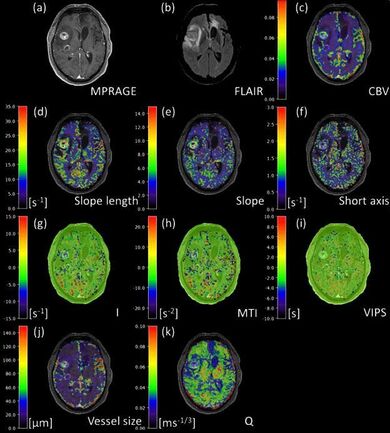

Die Arbeitsgruppe Translational Modelling beschäftigt sich mit der Entwicklung von Methoden und Modellen zur Quantifizierung funktioneller und struktureller Veränderungen von Gefäßen und Nervengewebe und deren Extrapolation und Einbindung in die klinische Routine. Dabei werden neue MR-Techniken wie das Vessel Architectural Imaging, das Arterial Spin Labeling, Relaxometrie und Mapping-Techniken bei 3 Tesla, 7 Tesla und 9.4 Tesla, sowie in Kooperation mit dem Deutschen Krebsforschungszentrum hochaufgelöste Multiphotonen-Mikroskopie und Lichtscheibenfluoreszenzmikroskopie eingesetzt. Die daraus erfolgende quantitative Charakterisierung von Gefäßnetzwerken und Nervengewebe dient als Grundlage für die Entwicklung von funktionellen Simulationen, welche die Veränderungen des MR Signals unter wechselnden physiologischen Bedingungen untersuchen. Die Arbeitsgruppe verbindet damit translational MR-physikalische Grundlagen, statistische Bildverarbeitung, präklinische Krankheitsmodelle und klinische Anwendung.

- Vessel architecture imaging using multiband gradient-echo/spin-echo EPI. Zhang K, Yun SD, Triphan SMF, Sturm VJ, Buschle LR, Hahn A, Heiland S, Bendszus M, Schlemmer HP, Shah NJ, Ziener CH, Kurz FT. PLoS One. 2019;9;14(8):e0220939.